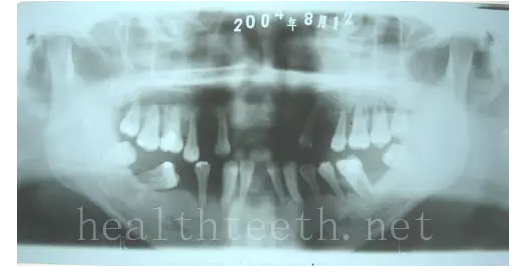

青少年牙周炎,20多歲牙齒破壞到這個程度

掌跖角化-牙周破壞綜合征(一種家族遺傳病在牙周的表現(xiàn))